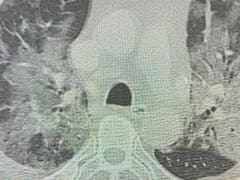

El Hospital de la Universidad George Washington publicó un video para mostrar la evolución del coronavirus en los pulmones: grabaron una tomografía en realidad virtual 360° muestra los efectos del coronavirus en los pulmones de un hombre de 59 años.

“Quiero que la gente vea la tomografía y entienda el daño que este virus puede hacer , dijo Dr. Keith Mortman, jefe de Cirugía torácica del Hospital de la Universidad George Washington.

Las áreas en amarillo muestran la rápida propagación de la infección y la inflamación en ambos pulmones. La inflamación ocurre cuando el cuerpo intenta controlar la infección, causando falta de aire al paciente.

Días antes, el paciente se presentaba como asintomático. Hoy, el paciente del video está con respirador y continúa en condición crítica en terapia intensiva.